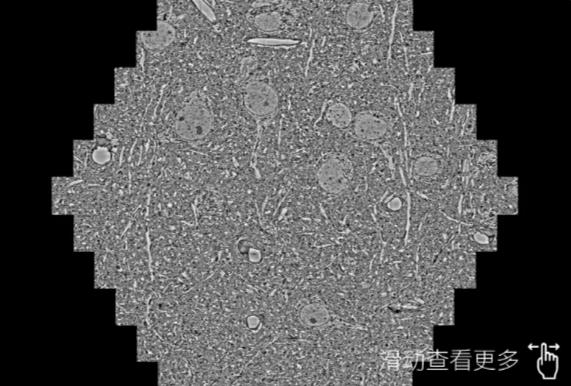

鼠脑切片。左图使用乐山蔡司乐山扫描电镜MultiSEM706对165μmx143pm面积区域成像,耗时仅需1.5秒。右图为鼠脑切片中30μm区域放大效果。样品由芝加哥大学B.Kasthuri提供。

使用蔡司高速乐山扫描电镜MultiSEM对1mm²人脑皮层组织进行高分辨成像,并对其中的各种细胞结构进行三维重构分析。左图展示了2x3mm²组织平面中锥体神经元的三维重构效果。右图显示了局部体积神经元三维重构。图像由哈佛大学chtman实验室提供,渲染图由D. Berger 制作。